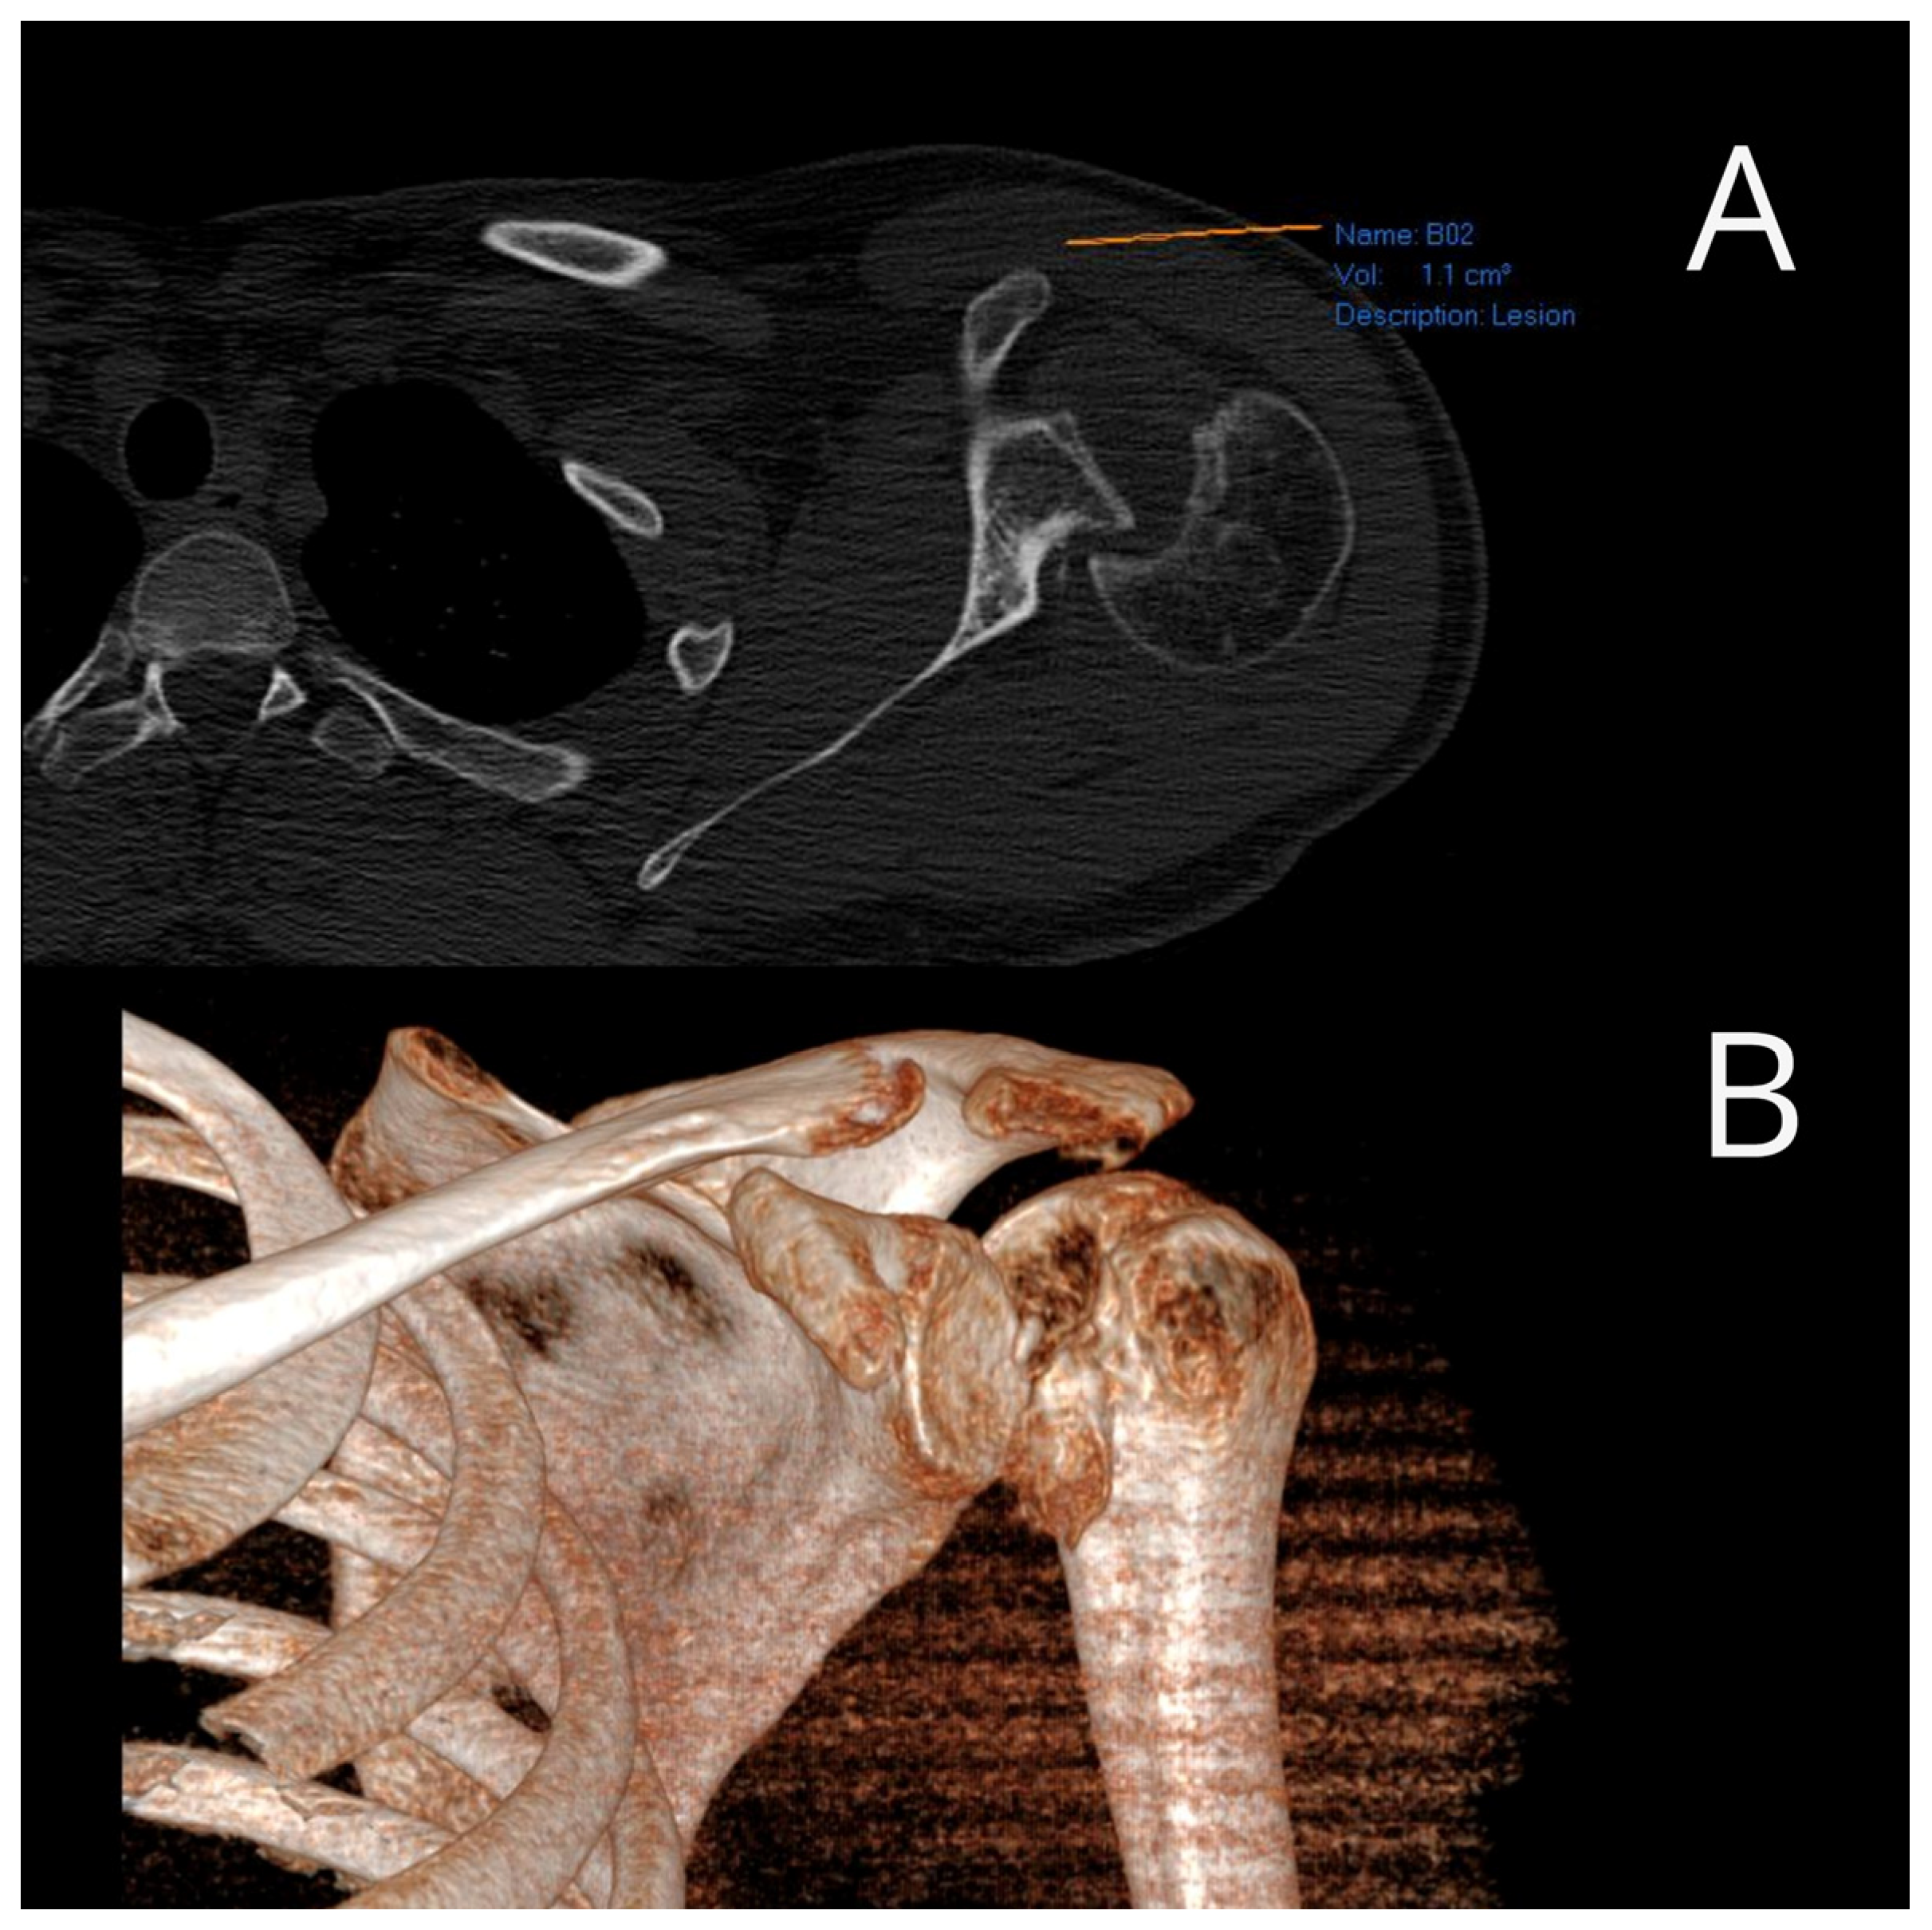

All examinees signed their informed consent. Patients underwent surgery at the Clinic for Orthopedic Surgery and Traumatology of the University Clinical Center of Vojvodina. Electrocution was the cause of injury in eight patients, direct trauma in ten patients and a fall due to hypoglycemic coma in two patients. There was no positive family history among the patients, and all injuries were unilateral. Eighteen patients had injured their dominant hand. Prior to the surgery, all patients underwent computed tomography (CT) scans to quantify the reverse Hill–Sachs lesions (Figure 1).

Following the confirmation of the diagnosis through traditional radiography, all patients underwent computed tomography (CT) scans. The dimensions of the defect in the humeral head were gauged using the preoperative CT scan while the head was dislocated posteriorly. A circular marker was placed over the humeral head in the CT scan taken at or just below the coracoid level. The cartilage angle was determined by two lines extending from the center of the circle to the cartilage immediately adjacent to the lesser tuberosity and the posterior end of the cartilage adjacent to the infraspinatus insertion. Another angle, referred to as the defect angle, was calculated by measuring the angles formed by connecting the anterior limit and posterior limit of the defect with the center of the humeral head. The size of the humeral head defect was estimated by determining what percentage of the cartilage angle the defect angle represented. A posterior glenoid rim defect that exceeded half of the maximum anteroposterior diameter was considered clinically significant.

Figure 1. Preoperative axial (A) and three-dimensional (B) CT image of a reverse Hill–Sachs lesion (photo from the personal archive of intraoperative photos of the author).